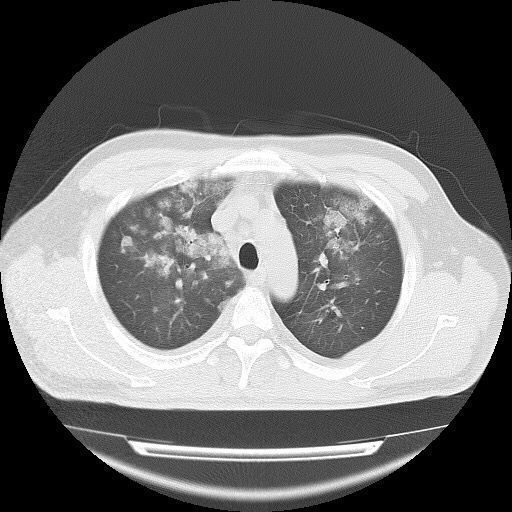

脑白质病变的影像表现与鉴别诊断 | 影像天地

呈均质较高密度,轻者钙化仅局限于苍白球,尾状核,壳核和丘脑,严重者

以苍白球钙化最常见.可同时见于尾状核和丘脑.

脑基底节:苍白球与尾状核可钙化,高龄者易出现,尤以 40 岁以后出现